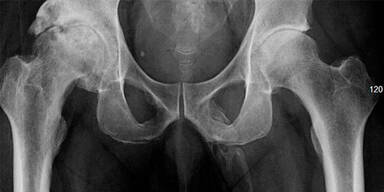

Die Ärzte machen ein Röntgen und machen darauf einen ungewöhnlichen Fund. Der 63-Jährige hat Knochengewebe an einer ungewöhnlichen Körperstelle: seinem Penis. Die Röntgenbilder zeigen, dass sich um den Penis des Mannes knochenähnliche Kalkablagerungen befinden. Der Patient gibt schließlich auch an, dass er Schmerzen in seinem besten Stück hat.